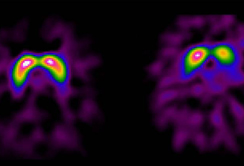

Das Parkinson-Syndrom stellt eine heterogene Gruppe von langsam fortschreitenden, neurologischen Erkrankungen dar, das auf das Absterben der Dopamin-produzierenden Nervenzellen in der Schwarzen Substanz – einer Struktur im Mittelhirn – zurückzuführen ist. Das Zellsterben führt zu einem Mangel des wichtigen Botenstoffes Dopamin und schließlich zur Entstehung der meisten, zentralen Symptome der Krankheit. Dazu zählen allgemeine Bewegungsarmut, Muskelsteifheit, Ruhe-Zittern sowie Gang- und Gleichgewichtsstörungen. Die Ursache des Zellschwundes in der Schwarzen Substanz wurde – mit Ausnahme einer erblichen Variante – bislang nicht gefunden. Parkinson ist deshalb bis heute nicht kausal, sondern ausschließlich symptomatisch behandelbar: Beispielsweise durch die Gabe von Medikamenten (Levodopa), die zu einer Erhöhung des Dopamin-Angebots im Gehirn führen sowie auch durch neurochirurgische Eingriffe. Parkinsonpatient:innen zeigen bis zehn Jahre nach der Diagnose gute Therapieerfolge, doch im weiteren Verlauf kommt es zu vermehrten Gleichgewichtsstörungen und Stürzen, einem Abbau der geistigen Leistungsfähigkeit und einer Zunahme nicht-motorischer Störungen.

Zahlreiche Studien, unter anderem auch aus Innsbruck, belegen, dass viele Parkinson-Patient:innen schon vor dem Auftreten der ersten motorischen Symptome andere Dysfunktionen entwickeln. Im Frühstadium werden etwa die chronische Obstipation (Verstopfung), aber auch Stimmungsstörungen mit Depressivität oder Panikattacken beobachtet. Aber auch die Störung des Geruchssinns und die nächtliche REM-Schlafstörung können frühe Indikatoren für das Parkinson-Syndrom sein. „Mindestens 50 Prozent der Patient:innen zeigen bis zehn Jahre vor Beginn der Krankheit derartige Symptome“, bestätigt Prof. Poewe ein Forschungsergebnis aus einer, in Zusammenarbeit mit Forscherkolleg:innen in Barcelona durchgeführten Untersuchung. Die „prämotorische“ Phase kann Monate bis Jahre in Anspruch nehmen und bildet somit ein wichtiges Zeitfenster für die Frühdiagnostik. Diagnostisches Potenzial liegt aber auch in der Bildgebung: So konnte in mehreren Studien die prädiktive Relevanz von Ultraschallmerkmalen im Mittelhirn bestätigt werden.